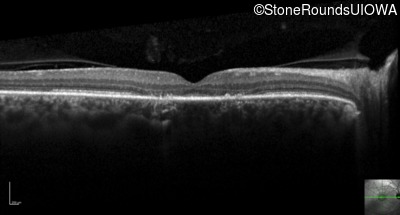

Optical Coherence Tomography - Left - 20/20 -1 sc

Exemplar / OCT Stack